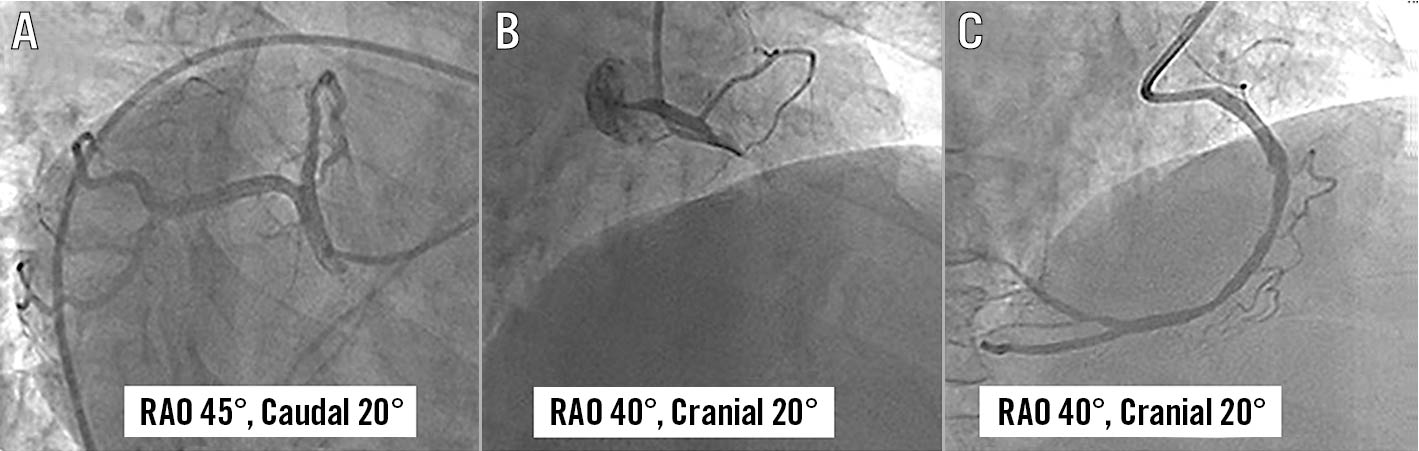

Figure 2. Coronary angiogram using the standard image display method in Case 1. Left coronary angiogram in right anterior oblique (RAO) 45°, caudal 20° (A) showed normal coronaries. Right coronary angiogram in RAO 40°, cranial 20° showed thrombotic occlusion of proximal right coronary artery (B), which was successfully stented (C).